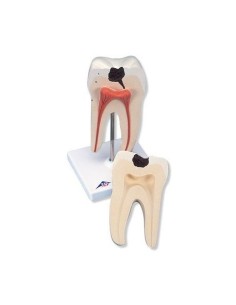

Erler Zimmer, modello anatomico di serie di morfologia dentale, ingrandito di 10 volte...

Erler Zimmer, modello anatomico di dente cariato, ingrandito di 10 volte D214